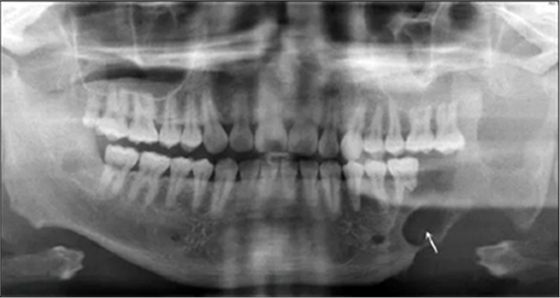

患者2014年6月5日因左下頜腫脹伴觸痛到青島大學(xué)附屬醫(yī)院口腔頜面外科就診,診斷為左側(cè)下頜骨成釉細(xì)胞瘤。全景片示左側(cè)下頜第二前磨牙遠(yuǎn)中至乙狀切跡處可見(jiàn)多房低密度影,左下頜第一磨牙遠(yuǎn)中根可見(jiàn)明顯吸收(圖1)。